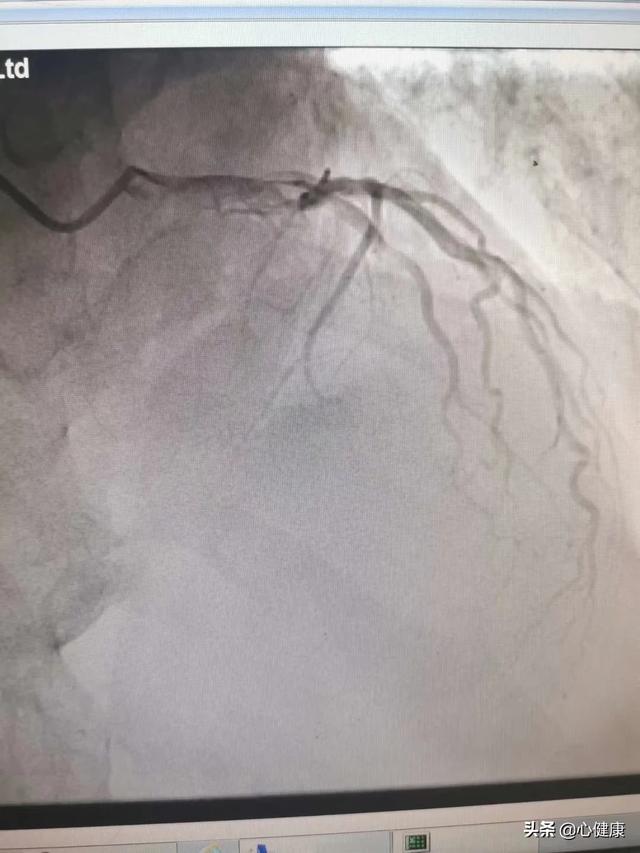

心脏造影,准确的来说是冠脉造影,这只是一个检查,来了解心脏表面的给心脏供应血液的血管(冠状动脉)壁上是否存在动脉粥样硬化斑块?如果有,造成血管腔的狭窄程度又如何,从而判断是否患有冠心病,这也是诊断冠心病的金标准。

心脏造影是心血管的常见检查,是诊断和治疗冠心病的一种常见方法,在一定程度上说,心脏造影是诊断冠心病的“金标准”;也就是说有没有冠心病,有没有心血管狭窄,做个造影就知道了!

冠脉造影是什么?

冠脉造影是冠心病确诊的金标准,更是一种侵入性检查,对患者有一定的伤害性,所以并不能像其他检查一样,想做就做,一般需要专业医师的判断后,方可进行。